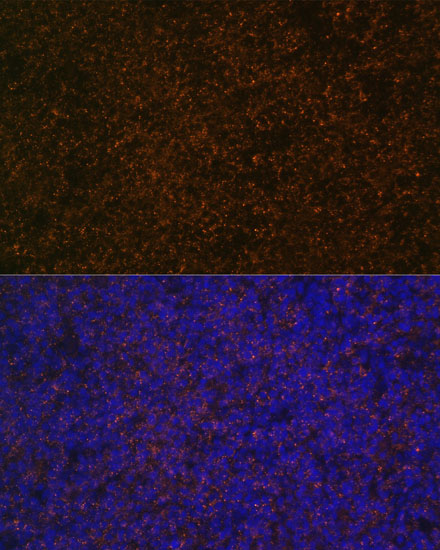

ApplicationWB, IHC, IF; Recommended dilution: WB 1:500 - 1:1000, IHC 1:50 - 1:100, IF 1:50 - 1:100